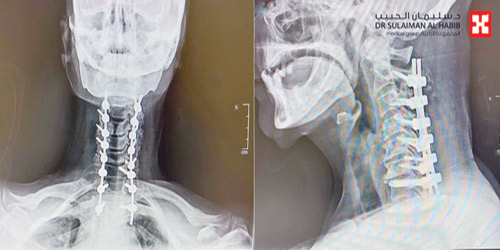

وقد أجريت للمريضة عملية تم فيها تحرير العمود الفقري من الضغط بإزالة الانزلاق الغضروفي وتثبيت الفقرة الرقبية رقم «2» وتوصيلها مع الفقرات الصدرية، تحت جهاز المراقبة العصبية، واستمرت العملية لنحو 3 ساعات ومضت بسلاسة وانتهت -ولله الحمد - بالنجاح التام. ونقلت المريضة من غرفة العمليات إلى غرفة التنويم، حيث أمضت «5» أيام، تحسنت حالتها خلالها مع الرعاية الطبية الحثيثة. كما استعادت السيدة قدرتها على المشي بعد نحو «36» ساعة من العملية، وغادرت المستشفى بحالة صحية ونفسية ممتازة، وقد تخلصت من معظم الأعراض التي جاءت بها إلى المستشفى، وتراجعت حدة المتبقي منها، وتحرَّرت من قيود ضعف الحركة وعادت لممارسة حياتها بلا آلام وبصورة طبيعية.